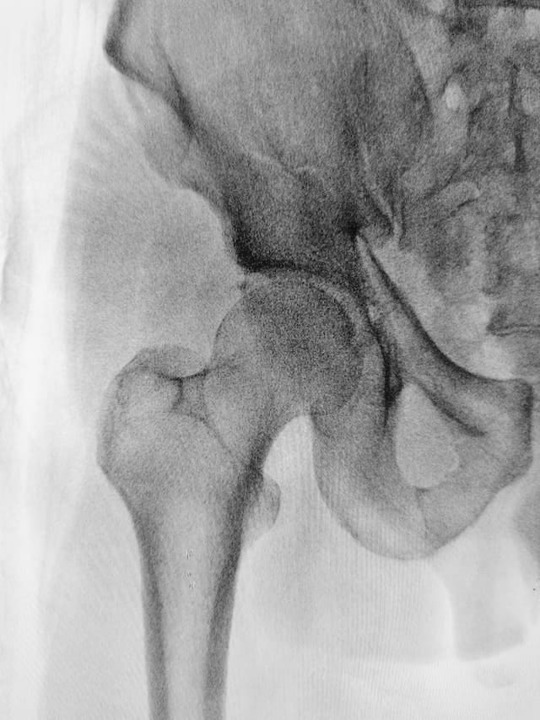

大腿骨頭すべり症を調べる時には、X線で両方の股関節を撮影します。大腿骨頭すべり症の場合は、大腿骨頭が大腿骨の残りの部分からずれたり、分離したりしていることがわかります。

大腿骨頭すべり症は、大腿骨の端部が股関節の成長板でずれたり分離したりした状態のことです。

大腿骨は太ももの骨のことで、大腿骨の上端の部分を大腿骨頭といいます。成長板は骨の端部に近い軟骨の柔らかい部分のことです。成長板から小児の骨は成長していきます。